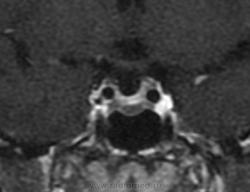

Ж, 37 лет. Наблюдается по поводу микроаденомы гипофиза, исследование в динамике. Предыдущие снимки сделаны в другом учреждении около года назад, картинка примерно такая же, однако на пленке отсроченные и постконтрастные снимки отсутствуют. В заключении была обозначена микроаденома округлой формы 3мм в диаметре.

Вот такая интересная картинка у нас получилась:

Постконтрастные:

И, наконец, отсроченные через 15 минут:

А вообще, отсроченное постконтрастное исследование в некоторых руководствах рекомендуется проводить, чтобы получить "инвертное" изображение - когда (микро)аденома накапливает контраст и становится гиперинтенсивной по сравнению с окружающей тканью гипофиза, откуда контраст уже к этому времени вымывается.

Не полупустой, в нижних отделах странной формы аденома. Плоская какая-то. За аденому то, что она хоть и медленно, но накапливает контраст, который в ней задерживается после того, как уже почти полностью вымылся из здоровой паренхимы аденогипофиза. Полупустой гипофиз (вернее полупустое турецкое седло, ещё вернее вторично "пустое" турецкое седло) получается после удаления аденомы. Или после самопроизвольного опорожнения кисты/кистозной аденомы гипофиза. 2 часа назд такое контролировал.

Нет, оказалось, что это вовсе не жидкость, а по характеру накопления парамагнетика - аденома необычной формы и локализации.

Известно только о 2х-кратном повышении пролактина, который на фоне консервативного лечения уменьшается до верхней границы нормы.